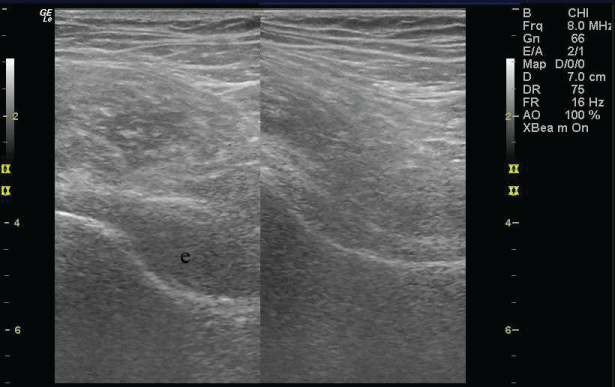

Considering the patient still experienced pain upon weight-bearing, on the follow-up examination, a diagnostic ultrasound (US) of both hip joints was performed by the physiatrist (Figure 1). Significant effusion of the right hip joint led to a magnetic resonance imaging (MRI) of both hip joints (Figure 2). The MRI revealed an ischemic lesion of the entire head and neck of the right femur with edema, including slight applanation of the femoral head and a small subchondral fracture (Steinberg classification system, grade I). Upon consultation with an orthopedic surgeon, the patient was referred for HBOT. Consequently, this choice of therapy was proposed for two months after the initial symptoms appeared.

Figure 1: Ultrasound examination of both hip joints. Effusion in the anterior synovial recess in the right hip (left side) vs. normal finding on the left hip (right side). e- marks effusion. View Figure 1

In our patient we opted for a MRI, when the first 10 treatments with physical therapy failed to show full mobilization of the right hip joint and after ultrasound detected significant effusion in the right hip joint (Figure 1). The MRI showed significant bone marrow edema and a small subchondral fracture with only slight applanation of the femoral head, which placed this patient in grade I of ARCO classification, and therefore suitable for HBOT.